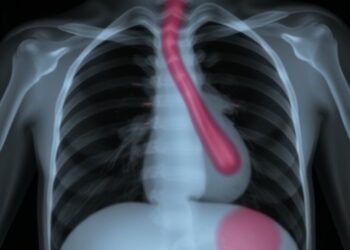

Child’s Left Pulmonary Aplasia and Artery Agenesis Case

In a remarkable case documenting a rare confluence of anatomical abnormalities, researchers from Nepal have illustrated the profound implications of ...